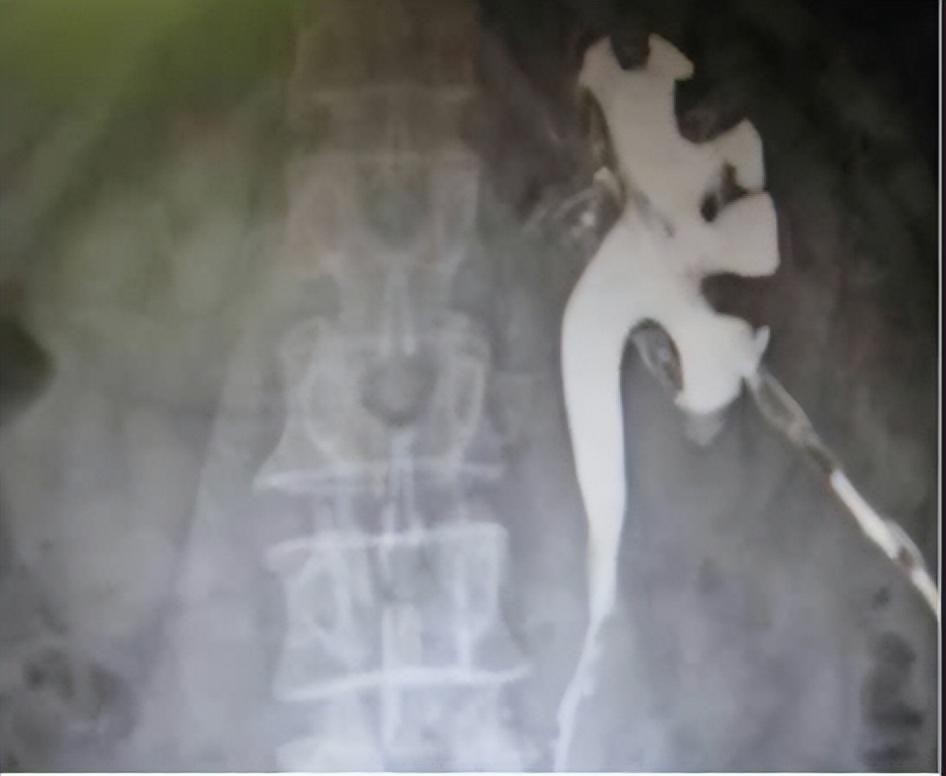

临床上怎么诊断乳糜尿?乳糜尿的临床诊断主要有: 反复出现乳白色或伴有红色的尿液,尿乳糜试验阳性,尿液中检出乳糜。膀胱镜检查可明确乳糜来源于何侧;影像学检查包括淋巴管造影、淋巴管造影CT、核素淋巴显像及MR淋巴成像等,有助于诊断乳糜尿并显示淋巴管瘘的位置和异常扩张淋巴管的分布情况[3]。